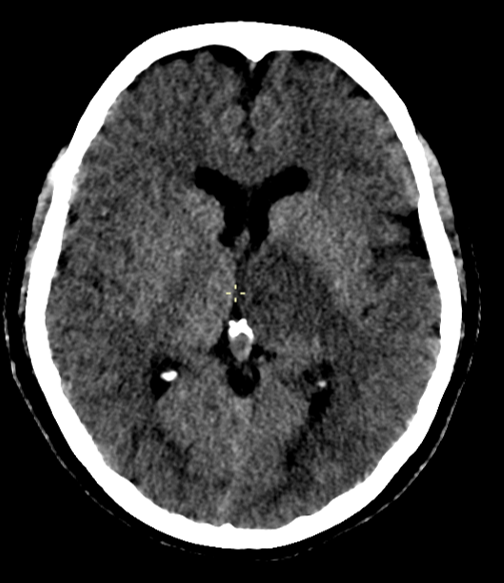

Une lésion profonde